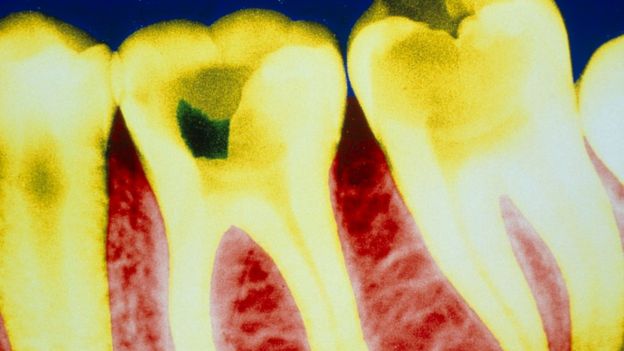

La caries está causada normalmente por la actividad de la placa bacteriana, que genera ácidos que dañan el esmalte de los dientes.

Las caries son la enfermedad dental más común en todo el mundo. Se caracteriza por la destrucción de los tejidos del diente y puede generar una inflamación del nervio dental que causa dolor.

Los dientes tienen naturalmente una cierta capacidad regenerativa: pueden producir una fina capa de dentina cuando la pulpa dental se queda expuesta.

La dentina, también llamada marfil o sustancia ebúrnea, es el tejido intermedio entre el esmalte dental, la capa externa más fuerte, y la pulpa, el tejido conectivo en el interior del diente.

Pero esa capacidad regenerativa natural es limitada: no puede reparar una gran cavidad.